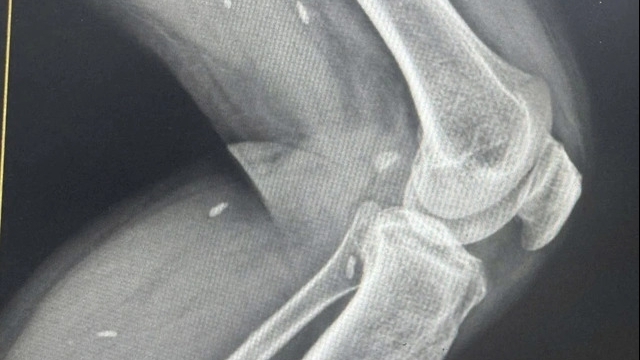

Sau khi nhập viện, tình trạng của thai phụ này đột ngột trở nên nguy kịch, glasgow chỉ còn 3 điểm, đồng tử hai bên giãn, hôn mê sâu, gần như rơi vào tình trạng chết não. Các bác sĩ ngay lập tức đặt ống nội khí quản, bóp bóng, cấp cứu đường thở cho bệnh nhân. Đồng thời tiến hành siêu âm ngay tại buồng cấp cứu, nhận thấy vẫn còn tim thai, bệnh nhân được đưa đi chụp phim cắt lớp vi tính thấy có khối máu tụ màng cứng rất lớn bán cầu phải. Một cuộc hội chẩn đã nhanh chóng diễn ra giữa các y bác sĩ với quyết tâm cứu lấy mẹ con sản phụ. Khoảng hơn 20 phút sau khi vào viện, chị C. được đẩy thẳng vào phòng mổ.